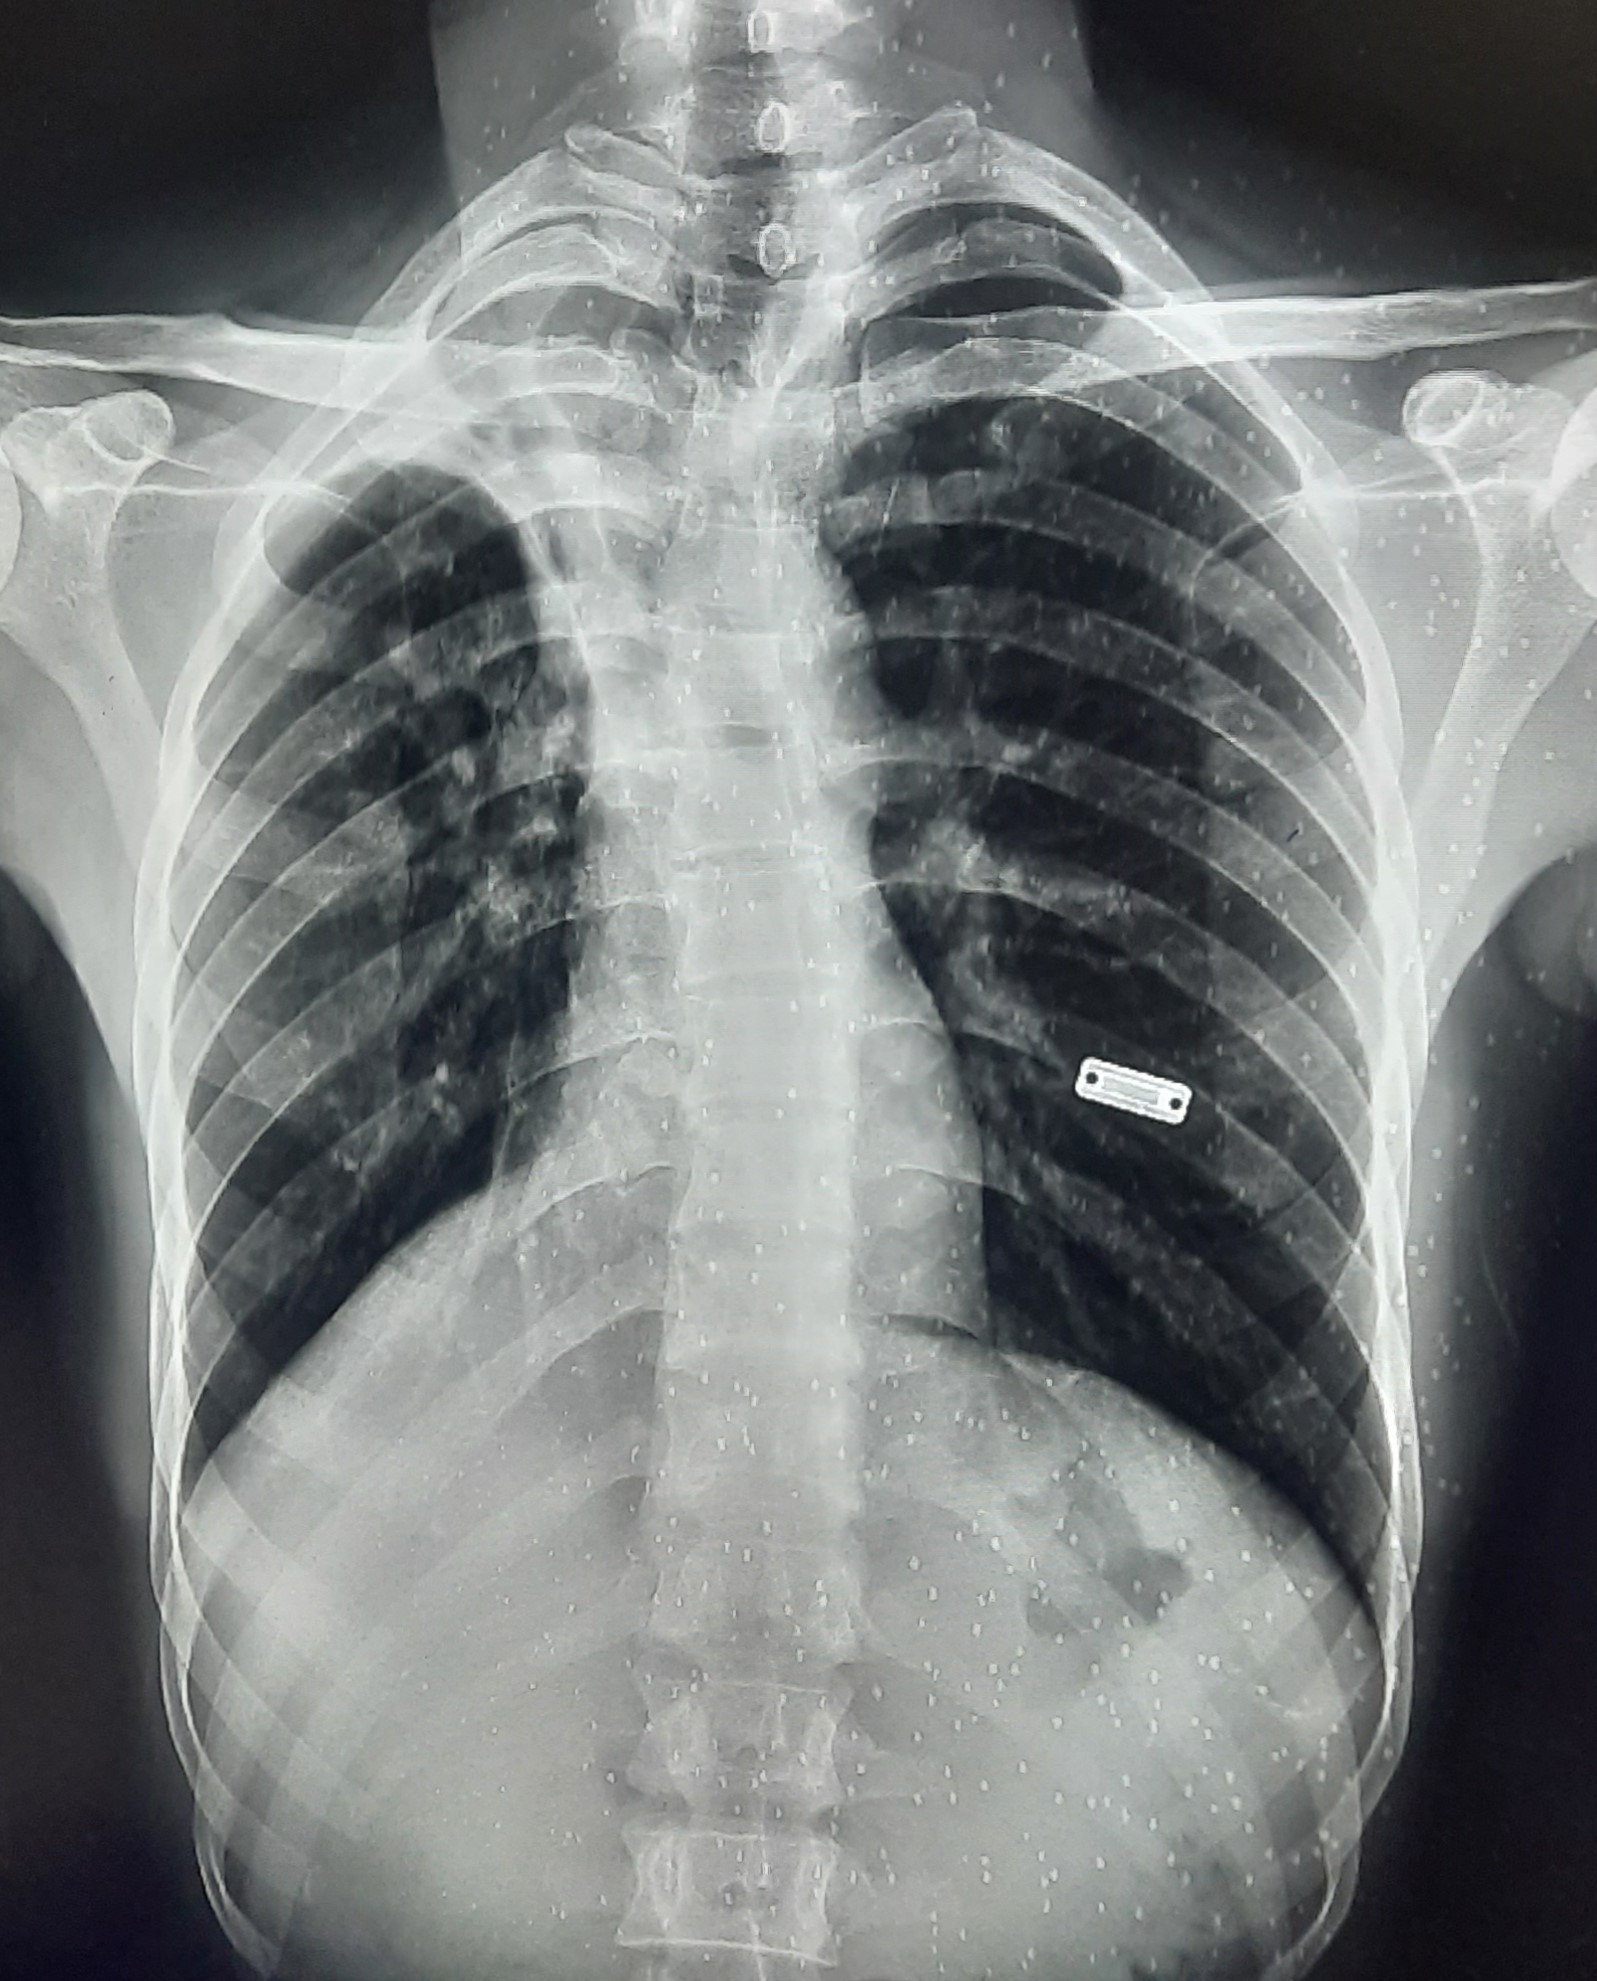

| 220 | IGGMC, Nagpur, Nagpur | P2 | 29-4252 | AMOL PAUNIKAR | Consent taken on Paper | 36 Yrs. |

Provisional Diag : BILATERAL INFILTRATION ? MILLIARY TB

Final Diag : MILLIARY TB |

TB Case (Confirmed) | MILLIARY TB | Abnormality visible on x-ray |

View |

|||